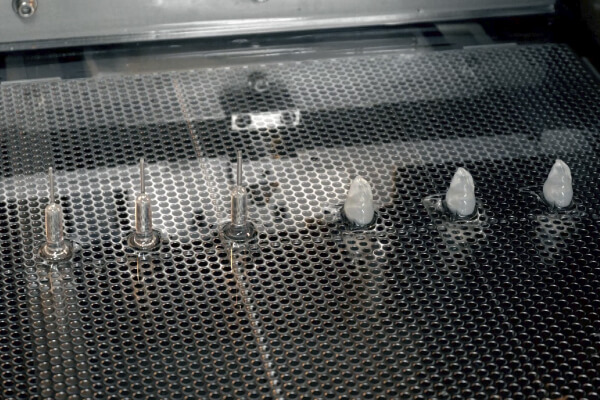

JMC's medical model fabrication service uses 3D printers and other digital technologies to achieve a high degree of freedom in model fabrication. 3D printed resin models are combined with vacuum casting technology to transfer the shape onto transparent, soft, and other materials. By combining 3D printed resin models with vacuum casting technology, we are able to transfer shapes onto transparent, soft, and other materials, providing services that thoroughly pursue the shapes, textures, and functions that customers demand.

In general, soft models often fail to reproduce some shapes, such as simplifying the inside of organs, but JMC Lab possesses a unique technology that combines 3D printing and casting technologies to faithfully reproduce the outside and inside of organs. JMC Lab has a unique technology that combines 3D printing and casting techniques to faithfully reproduce the outside and inside of organs. This method allows for a higher degree of material flexibility than direct 3D printing of soft materials, and allows for adjustments in hardness, color, X-ray transmission, etc.

We have a system in place that allows us to work 24 hours a day, 7 days a week on rigid models that are output directly from the 3D printer, so that we can deliver them quickly to our customers in fields that require speed, such as preoperative simulation and prototyping of medical devices. We have a variety of output methods, including optical, SLS, and inkjet, so you can choose the most suitable method for your application.